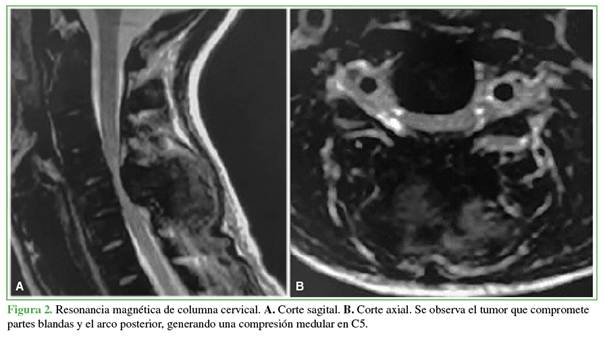

Se solicitaron radiografías y una tomografía computarizada de columna cervical que mostraron una voluminosa lesión osteolítica con márgenes esclerosos en el arco posterior de la 5.a vértebra cervical y extensión a partes blandas adyacentes de dicha región (Figura 1). En la resonancia magnética, se observó una compresión medular severa en la 5.a vértebra cervical (Figura 2).

El tumor pardo, en particular, suele aparecer en la radiografía o el estudio tomográfico como una imagen lítica, multilobulada que puede o no contener márgenes periféricos esclerosos. En la resonancia magnética, se observa una lesión hipointensa en la secuencia T1 e hiper/isointensa en la secuencia T2 con tendencia a la invasión de tejidos adyacentes; cuando se administra un medio de contraste intravenoso suele realzarlo.7,8

En nuestra paciente, el compromiso de la lesión se extendía a todo el arco posterior de C5 y afectaba no solo a las partes blandas paravertebrales, sino también la región epidural posterior generando una compresión medular significativa.